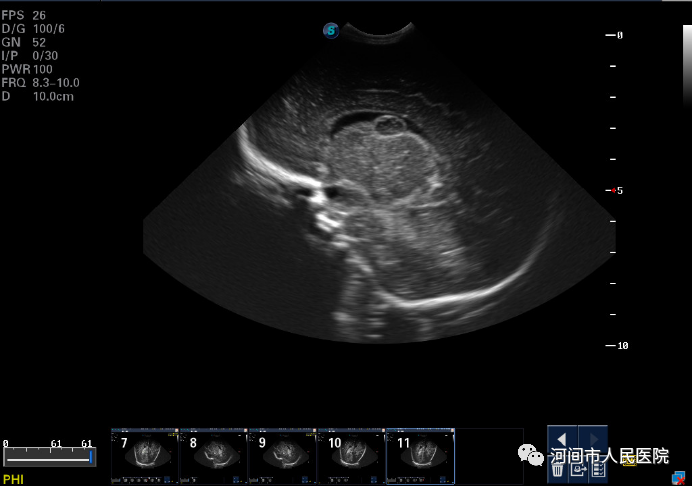

▲新生儿缺血缺氧性脑病